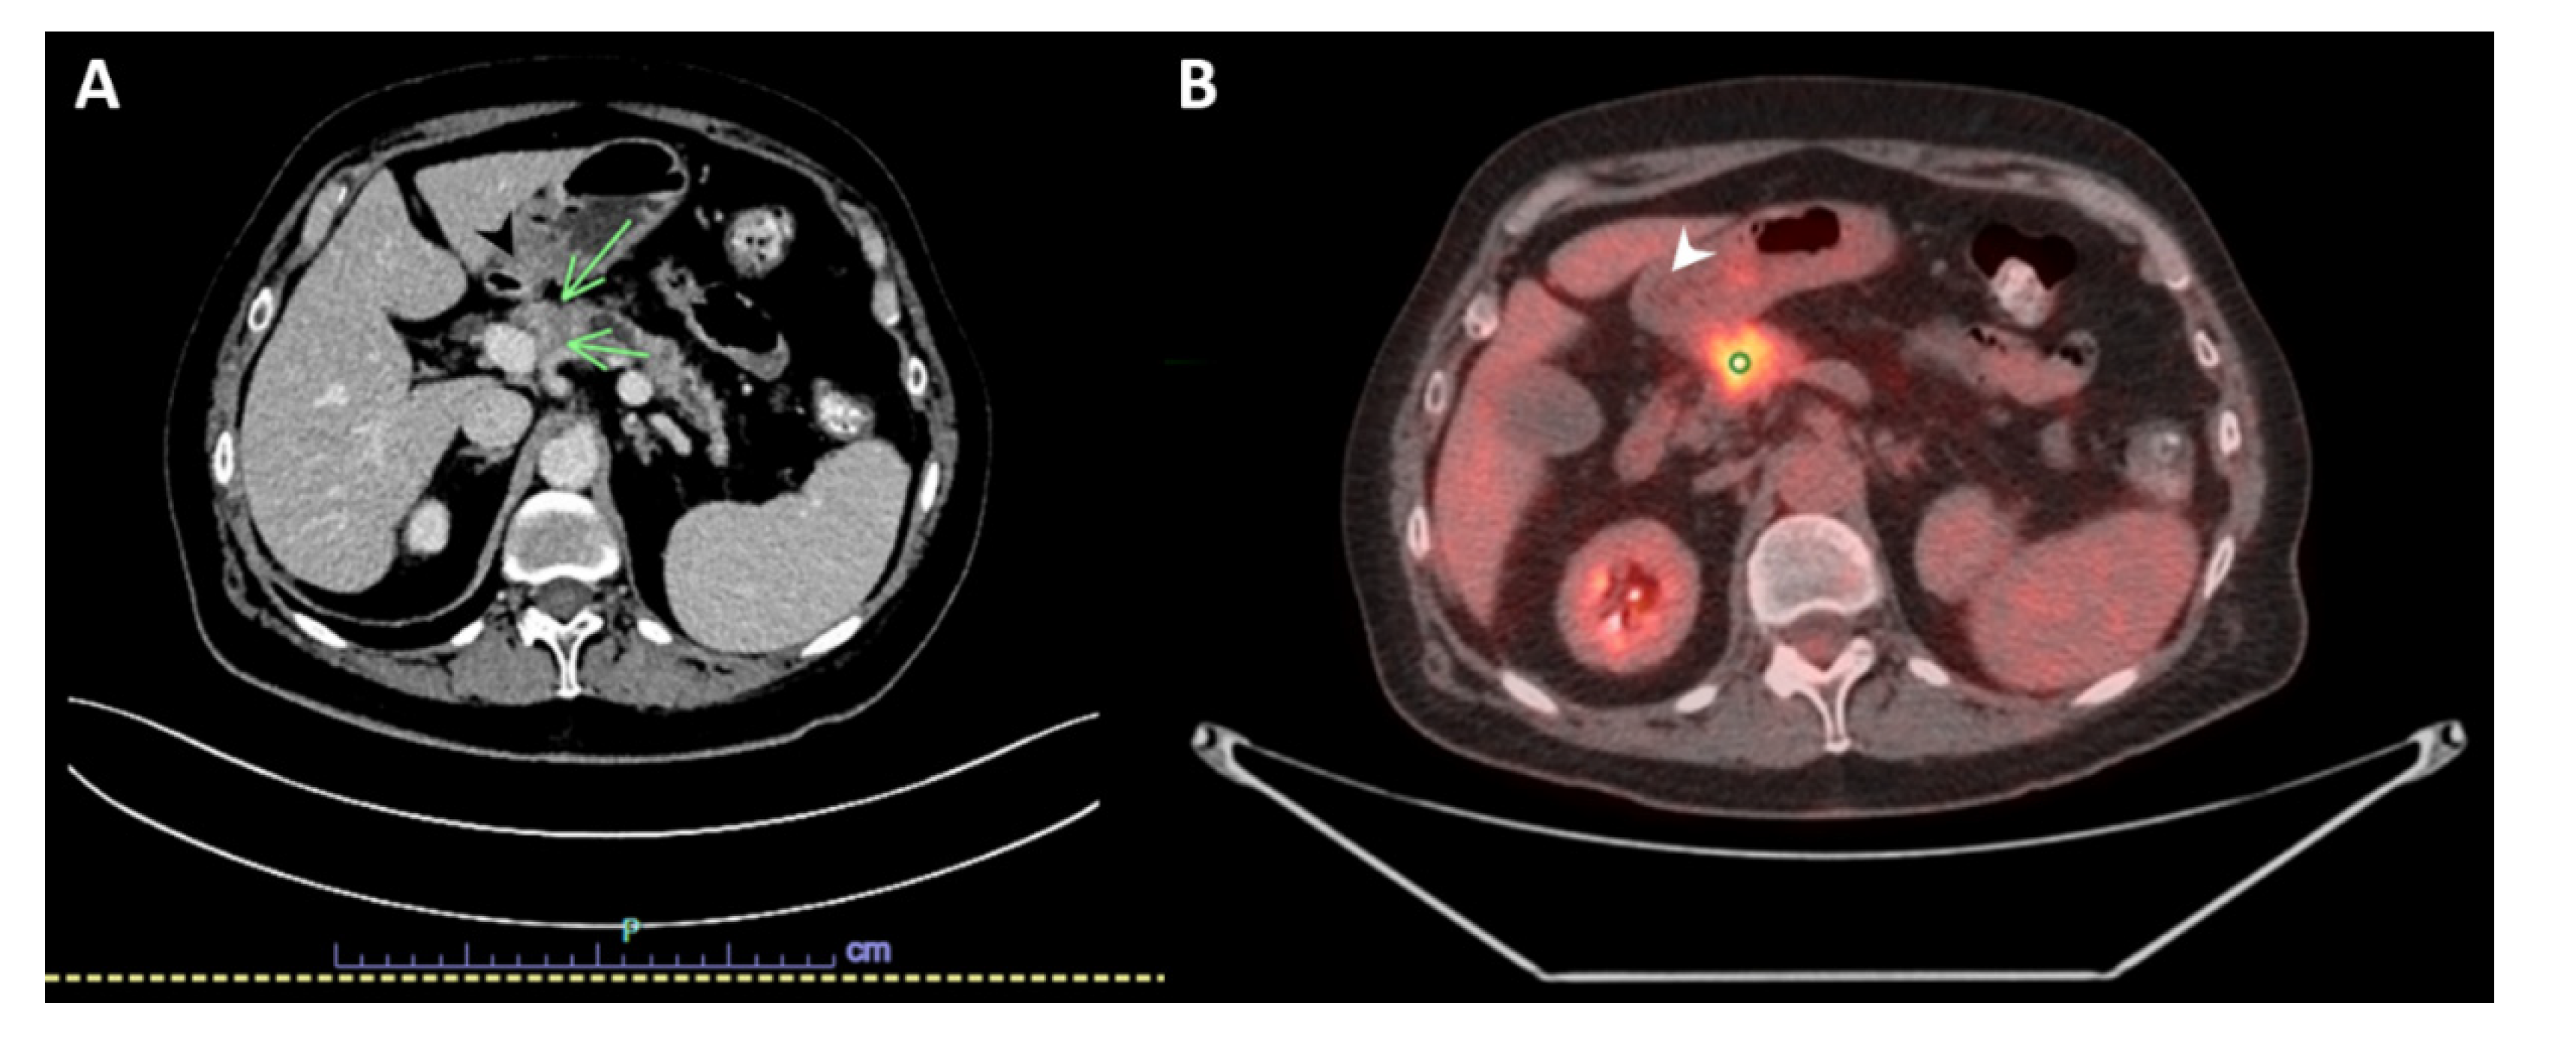

A 69-year-old woman with a history of primary left lung adenocarcinoma (confirmed and supported by immunohistochemical (IHC) stains) in 2014 that was treated with post left upper lobe resection and Cisplatin-based chemotherapy (treated at another institution), and contralateral primary lung adenocarcinoma in 2016 (confirmed and supported by IHC stains as well), which was treated at another institution with a right wedge resection, presented to our institution with abdominal discomfort. A computed tomography (CT) scan of the abdomen and pelvis with IV contrast demonstrated a hypoenhancing pancreatic mass centered in the pancreatic neck, measuring 2.7 cm in greatest dimension, with a dilatation of the upstream main pancreatic duct (up to 7 mm in diameter) and atrophy of the upstream pancreatic parenchyma that was consistent with pancreatic malignancy. The mass appeared to be abutting the splenoportal confluence with mild to moderate stenosis of the splenic vein, moderate stenosis of the superior mesenteric vein, and mild stenosis of the main portal vein at the confluence (Figure 1A). An abdominal positron emission tomography (PET)/CT scan was performed in April 2021, and showed a mildly enlarged pancreas with a 2.7 cm heterogeneous, hypoechoic mass in the head of the pancreas with abnormal hypermetabolic uptake in the SUV MAX 9.3. Multiple subcentimeter peripancreatic lymph nodes were seen without abnormal hypermetabolic uptake (Figure 1B).

Figure 1.

Imaging studies. (A) Computed tomography (CT) scan with IV contrast of the abdomen and pelvis showing a hypoenhancing pancreatic mass centered in the pancreatic neck, measuring 2.7 × 2 cm (green arrows). (B) Positron emission tomography (PET)/CT scan of the abdomen demonstrating mildly enlarged pancreas with a 2.7 cm heterogeneous, hypoechoic mass in the head of the pancreas with abnormal hypermetabolic uptake in the SUV MAX 9.3 (white arrow).